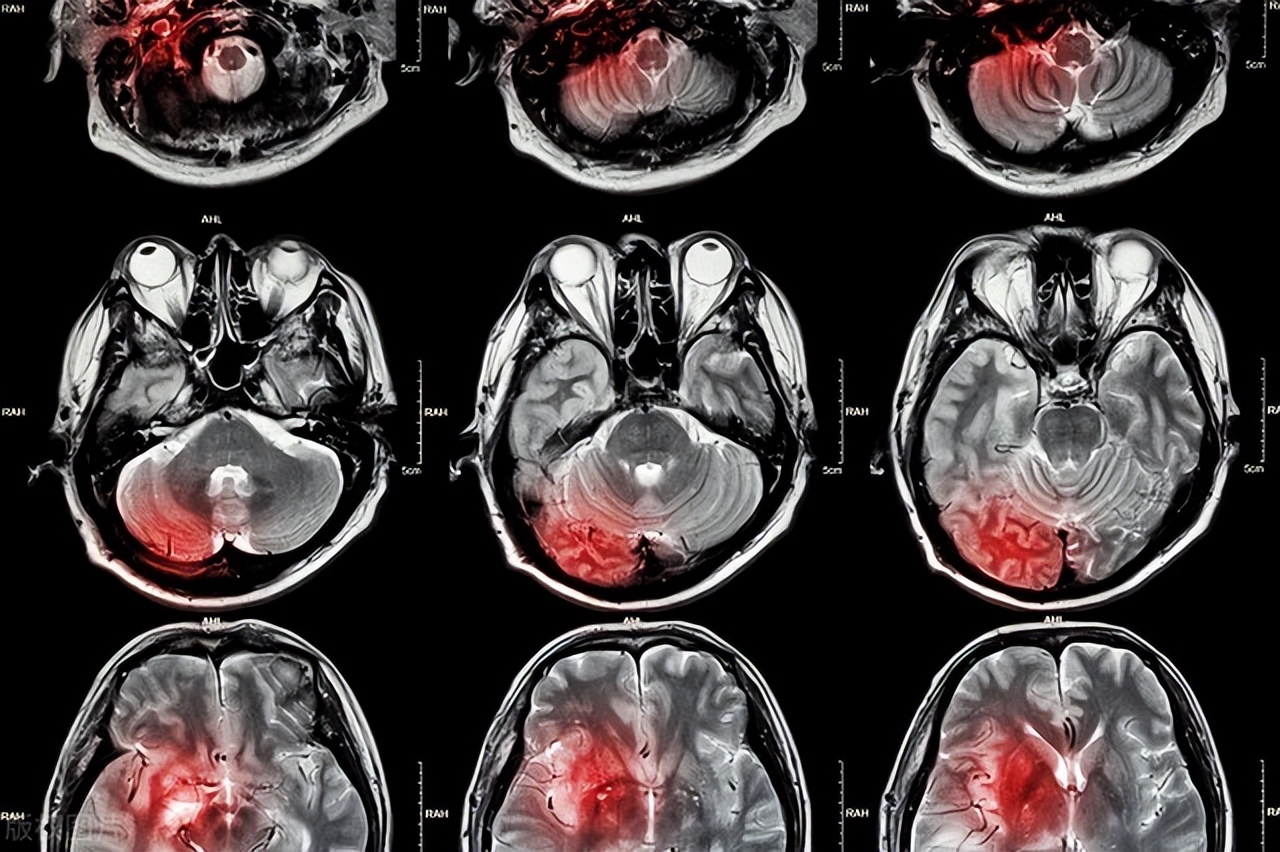

突发脑出血是一种严重的脑血管疾病,由于脑部血管破裂或破裂引起的出血而引起。脑出血通常发生在脑室、脑干或脑皮层等区域,常常具有突发性和急性危害性。

脑出血的危害性非常大,可能导致永久性的神经功能障碍和死亡。出血量越大,对神经系统的影响就越严重。一旦出现脑出血的症状,需要及时采取应急措施,寻求医疗帮助并进行及时治疗。